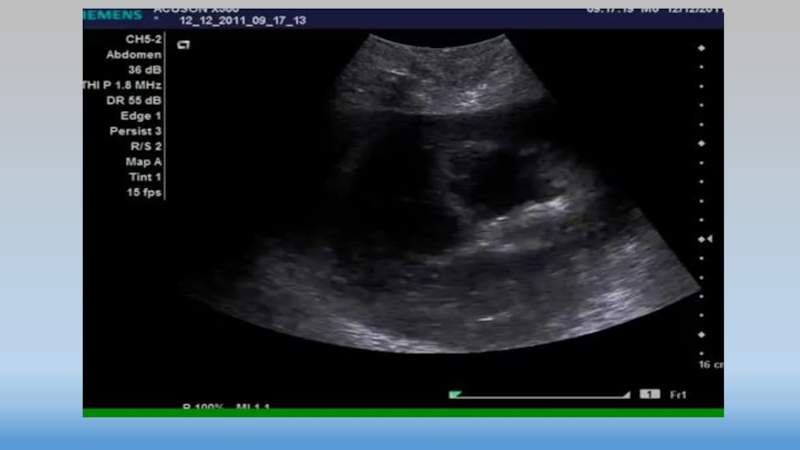

Слайд 18Точки 3-4

Точки 3-4

Слайд 20Точки 3-4